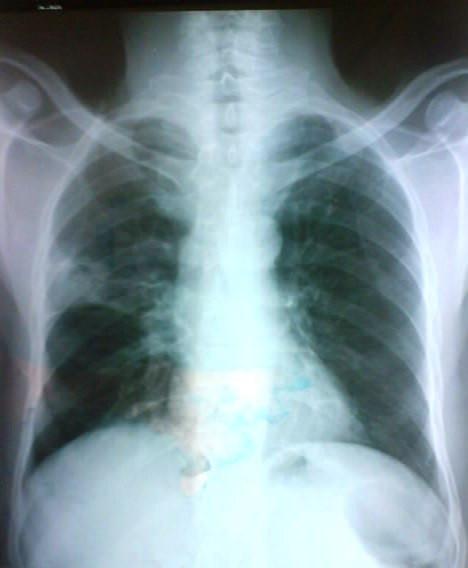

A 60 year old male with a long standing history of smoking was referred to our department for surgery of aspergilloma in right upper lung lobe diagnosed by computed tomography and confirmed by computed tomography guided needle aspiration biopsy. A lobectomy was performed. Histological study of the surgical specimen revealed a pulmonary adenocarcinoma associated with aspergilloma. By presenting this case we suggest that every case of pulmonary aspergilloma should be examined for malignancies, especially in smokers.

一位 60 岁男性,长期吸烟史,因 CT 诊断的右上肺曲霉球,并经 CT 引导下针吸活检证实,转入我科行手术治疗。行肺叶切除术。手术标本的组织学研究显示与曲霉球相关的肺腺癌。通过本例报告,我们建议对每个曲霉球病例都应检查恶性肿瘤,特别是在吸烟者中。